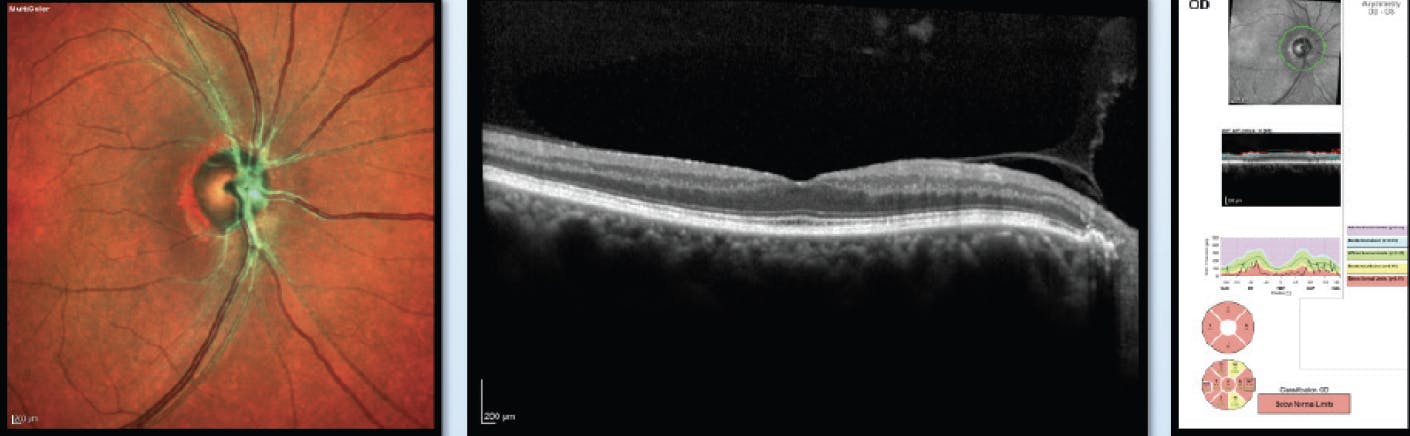

Neuromyelitis optica spectrum disorder (NMOSD), also known as Devic’s disease, is a chronic disorder of the brain and spinal cord dominated by optic neuritis and myelitis.2 Typically, NMOSD is unilateral although it can be bilateral. We originally thought these patients only had bad neuritis. However, multicolor OCT imaging shows that patients with NMOSD who have poor visual recovery develop an immunologically driven CRAO (Figure 3).

<p>Figure 3. These images show a patient who was seropositive for NMOSD. With CRAO and no current emboli, the green branches of the central retinal artery are consistent with CRAO and retinal ischemia. The multicolor imaging helps detect neuromyelitis optica along with peripheral blood aquaporin-4 antibody titer.</p>

Figure 3. These images show a patient who was seropositive for NMOSD. With CRAO and no current emboli, the green branches of the central retinal artery are consistent with CRAO and retinal ischemia. The multicolor imaging helps detect neuromyelitis optica along with peripheral blood aquaporin-4 antibody titer.

Based on histopathology, we now know that NMOSD is an autoimmune astrocyte disease,3 and we know that the retina has a large astrocyte population, especially in the Müller cells. In addition, other retinal cells can express aquaporin. When neuroradiologists look closely at the spinal imaging of patients with NMOSD, they will often see an ischemic pattern. Using multicolor OCT imaging, we now know that what is happening in the spinal cord with strokes also happens in the retina.

The other characteristic finding of NMOSD is transverse myelitis, which may be indistinguishable from other cases of “idiopathic” transverse myelitis. Early in the course of the disease, it may be difficult to distinguish between NMOSD and multiple sclerosis (MS) because both can cause optic neuritis and myelitis. However, optic neuritis and myelitis tend to be more severe in NMOSD; the brain MRI is more commonly normal, and the spinal fluid analysis does not usually show oligoclonal bands in NMOSD, which are features that help distinguish it from MS. NMOSD optic neuritis has a much poorer prognosis than MS optic neuritis, and the retina multicolor and OCT show that patients with NMOSD have greater retinal nerve fiber layer and ganglion cell loss than MS patients.